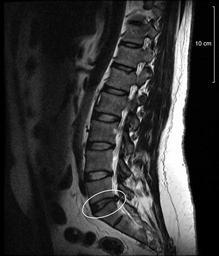

MAKE A MEME View Large Image Spinal-disc-protrusion-l5.jpg en MRI T2-image of a spinal disc protrusion in the left lateral recess at the L5 level compressing the left central nerve root Compared to a disc extrusion the still existing contrast in the disc indicates that ...

Keywords: Spinal-disc-protrusion-l5.jpg en MRI T2-image of a spinal disc protrusion in the left lateral recess at the L5 level compressing the left central nerve root Compared to a disc extrusion the still existing contrast in the disc indicates that no fluid has been extracted and thus the general structure of the disc is still intact This represents a pre-stage of a spinal disc herniation if the pressure on the disc is not lowered by improving the muscle structure of the back de MRT T2 Bild einer links subartikulären Bandscheibenprotrusion LWK5/SWK1 mit Impression der Nervenwurzel S1 links sowie einer Spondylarthrose LWK4/LWK5 und LWK5/SWK1 Der noch existierende Kontrast in der betroffenen Bandscheibe lässt auf einen noch nicht stattgefundenen Prolaps Vorfall schliessen und deutet auf eine noch intakte Bandscheibenstruktur hin kein Gallat ausgetreten Diese Art der Erkrankung stellt eine Vorstufe eines Bandscheibenvorfalls dar und kann zu einem Prolaps führen wenn keine Maßnahmen zur Stärkung der Rückenmuskulatur bzw zur Entlastung der Bandscheibe vorgenommen werden own Damato 2010-06-11 MRI of spinal disc herniation undefined Diseases and disorders of the musculoskeletal system Neurology Magnetic resonance imaging of the lumbar spine Orthopedics